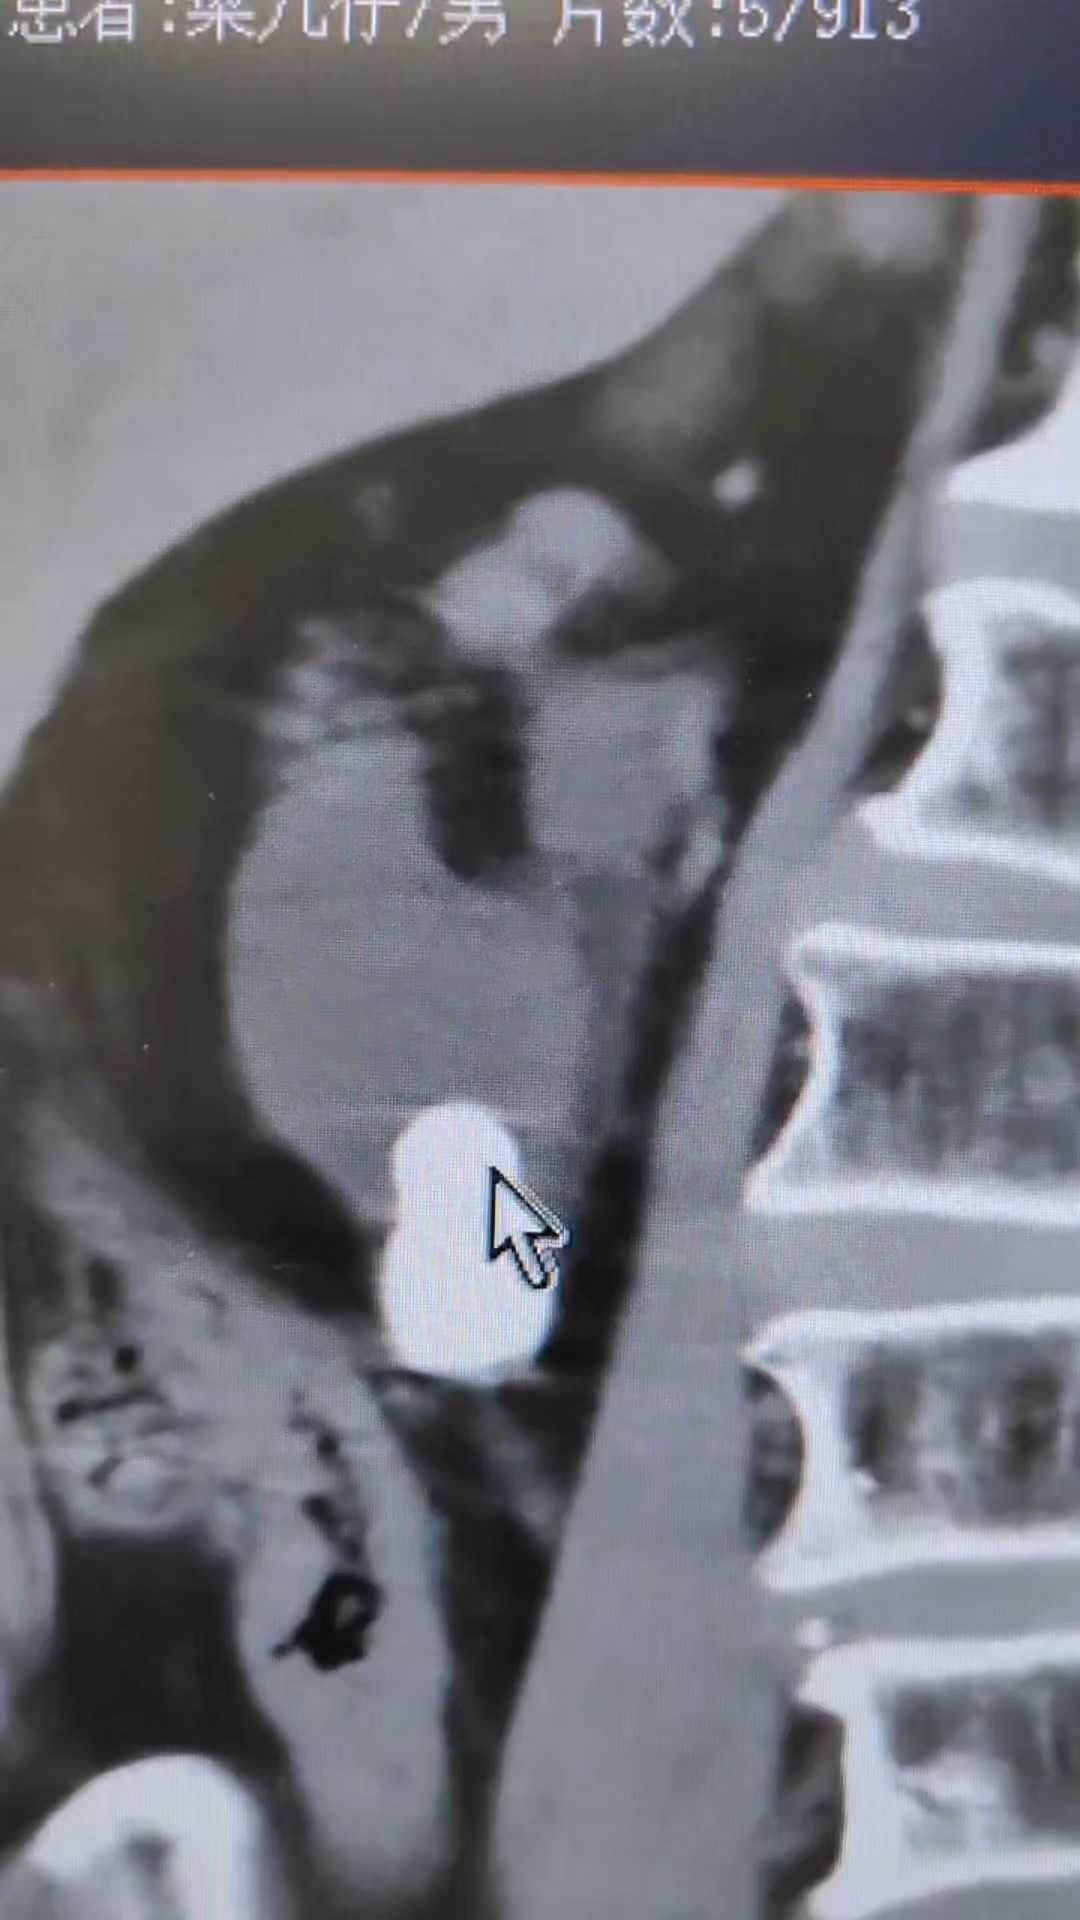

重复肾结石见过,重复输尿管结石见过,重复肾重复输尿管交汇的铸型结石还是少见

重复输尿管 (3)